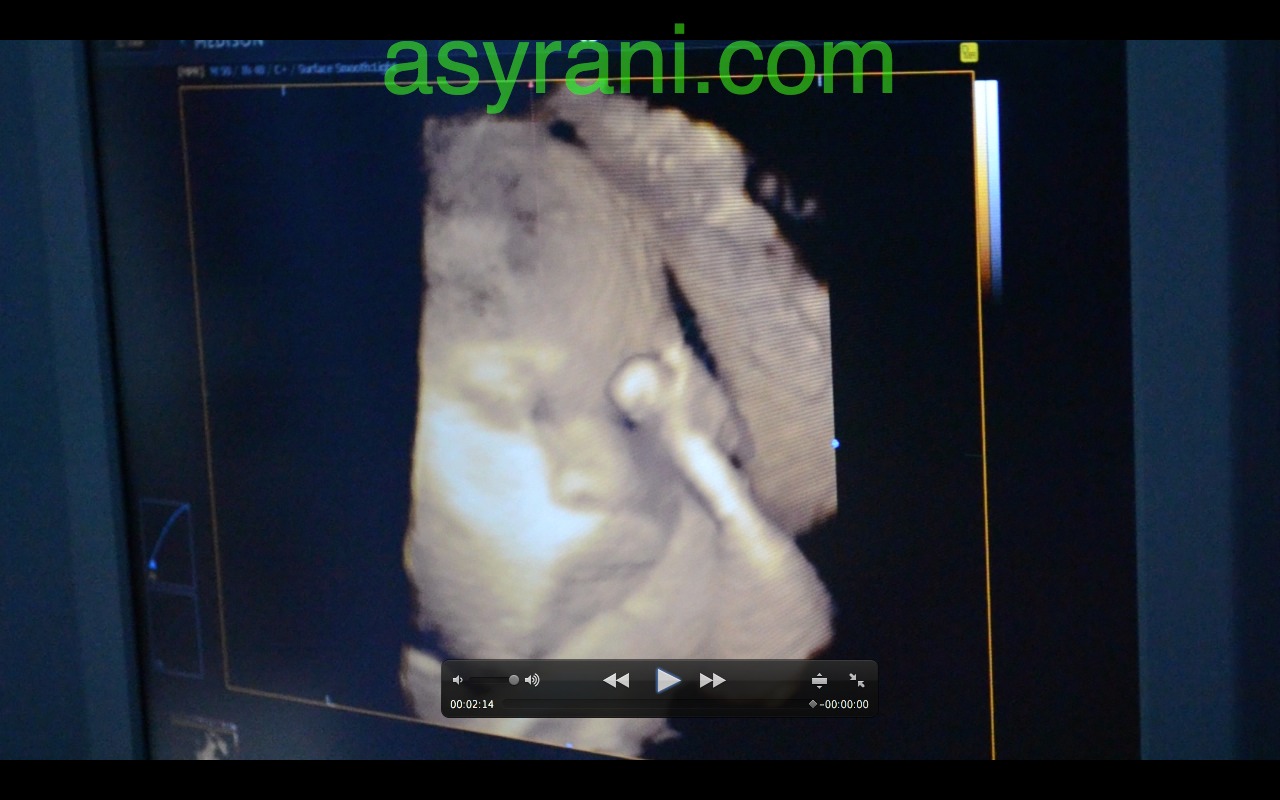

Muka baby dalam bentuk 3D. Kelihatan hidung, mata dan bibir atas. Yang lain tertutup oleh uri dan bayang-bayang uri

Gambar 3D scan yang jelas sedikit. Kelihatan tangannya menutup mata